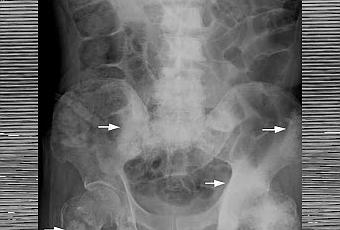

Adénocarcinome de la prostate avancé (...) présentant des métastases osseuses chez un homme de 70 ans.

Source iconographique et légendaire: https://commons.wikimedia.org/wiki/File:Osteoplastic_bone_metastasis_prostate_cancer_01.jpg